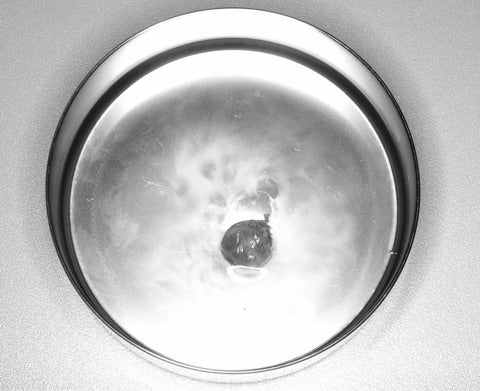

<摘出された嚢胞>